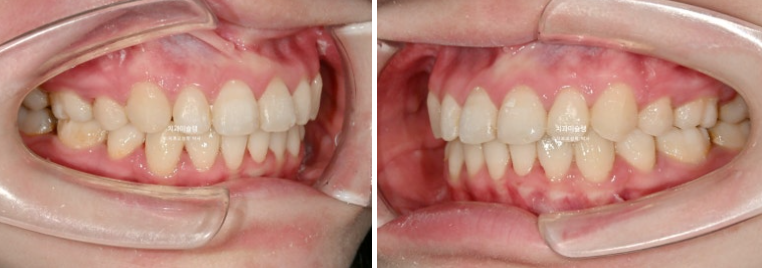

23년 8월 교정치료를 위해 내원한 환자분입니다.

23.08

위 아래 중심선은 어긋나 있고

윗니가 아랫니를 많이 덮어 아랫니가 잘 안보이는 심한 과개교합이 보입니다.

파란 화살표 부분은 위 아래 큰어금니가 엇갈려 물리는 가위교합입니다.

파란화살표 두번째 큰어금니가 바깥으로 밀려나가 가위교합이 된 것 입니다.

앞니도 많이 삐뚤합니다.